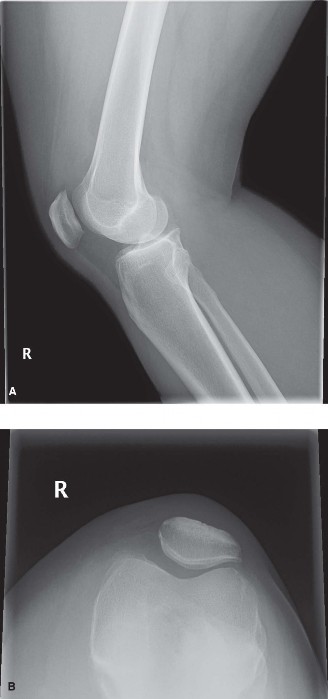

Standard radiographic evaluation of the knee is the first-line imaging modality for anterior knee pain. The patient's initial X-rays (Figures 9-1 A-C) include a weight-bearing anteroposterior (AP), a true lateral at 30 degrees of flexion, and an axial (Merchant or Sunrise) view.

The AP view demonstrates normal tibiofemoral joint spaces with no evidence of osteochondral lesions, loose bodies, or degenerative changes. The lateral view is scrutinized for patellar height. The Insall-Salvati ratio (the ratio of the patellar tendon length to the greatest diagonal length of the patella) is calculated at 1.05, which falls within the normal range (0.8 to 1.2), ruling out patella alta or baja. The lateral view also shows no evidence of trochlear dysplasia; the crossing sign is absent, and the trochlear bump is not prominent.

The Merchant view is arguably the most critical radiograph for this patient. It reveals a subtle lateral tilt of the patella and mild lateral subluxation. The sulcus angle measures 138 degrees (normal is typically <145 degrees), indicating adequate trochlear depth. However, the congruence angle is slightly lateralized, confirming the clinical suspicion of lateral patellar maltracking. There is no evidence of advanced patellofemoral osteoarthritis, osteophyte formation, or subchondral sclerosis.